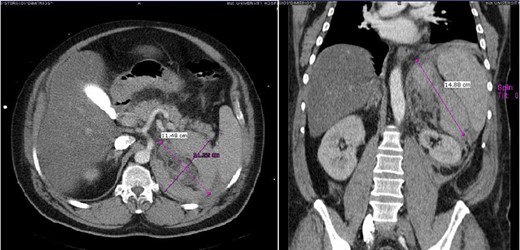

CASE REPORT 1

Case 1 presenting imaging (CT) showing a large left peri-adrenal hematoma.